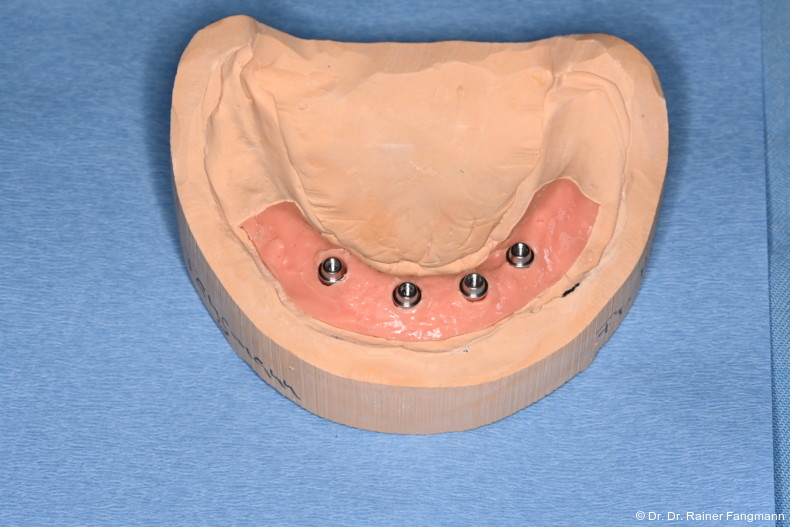

Wenn die geraden und/oder angulierten Basisaufbauten (Ankylos® Balance C/schmal) in situ sind, werden diese mit den Schutzkappen für Balance Basisaufbau schmal für die Zeit zum Schutz versorgt. In dieser Situation erfolgt entweder eine Situationsabformung oder ein Situationsscan. Im zahntechnischen Labor wird aufgrund dieser Basis ein Pattern-Resin-Steg hergestellt, der die Retentionskappe für Balance Basisaufbau schmal einbindet. Dieser Steg wird der Zahnarztpraxis getrennt angeliefert. Die Retentionskappen werden in situ eingebracht und mit der Halteschraube okklusal M 1,6 mm Hex extralang fixiert. Der getrennte Pattern- Resin-Steg wird intraoral mit dem gleichen Material verblockt. Danach erfolgte die typische Implantatabformung auf Abutmentniveau mit z. B. Dentsply Sirona Aquasil Ultra+ über einen laborgefertigten individuellen Abformlöffel. Im zahntechnischen Labor wird dann das klassische Meistermodell mit dem Basisaufbau entsprechend der Implantatanzahl hergestellt. Dieses wird samt der Unterkieferwachsaufstellung und dem Gegenkiefer, der auch 3D-gedruckt sein kann, und einer Bißnahme versandt. Der Auftrag wird vom Zahntechniker in der ATLANTIS-WebOrder parallel eingegeben. Die Suprastruktur wird erst nach einer Überprüfung und der endgültigen Freigabe des Designs im ATLANTIS ISUS-Viewer gefertigt. Die Implantat-Suprastruktur wird an das Dentallabor geliefert, das daraus die fertige Prothetiklösung herstellt und diese dem Zahnarzt schickt.

Fertigungstechniken für Stege